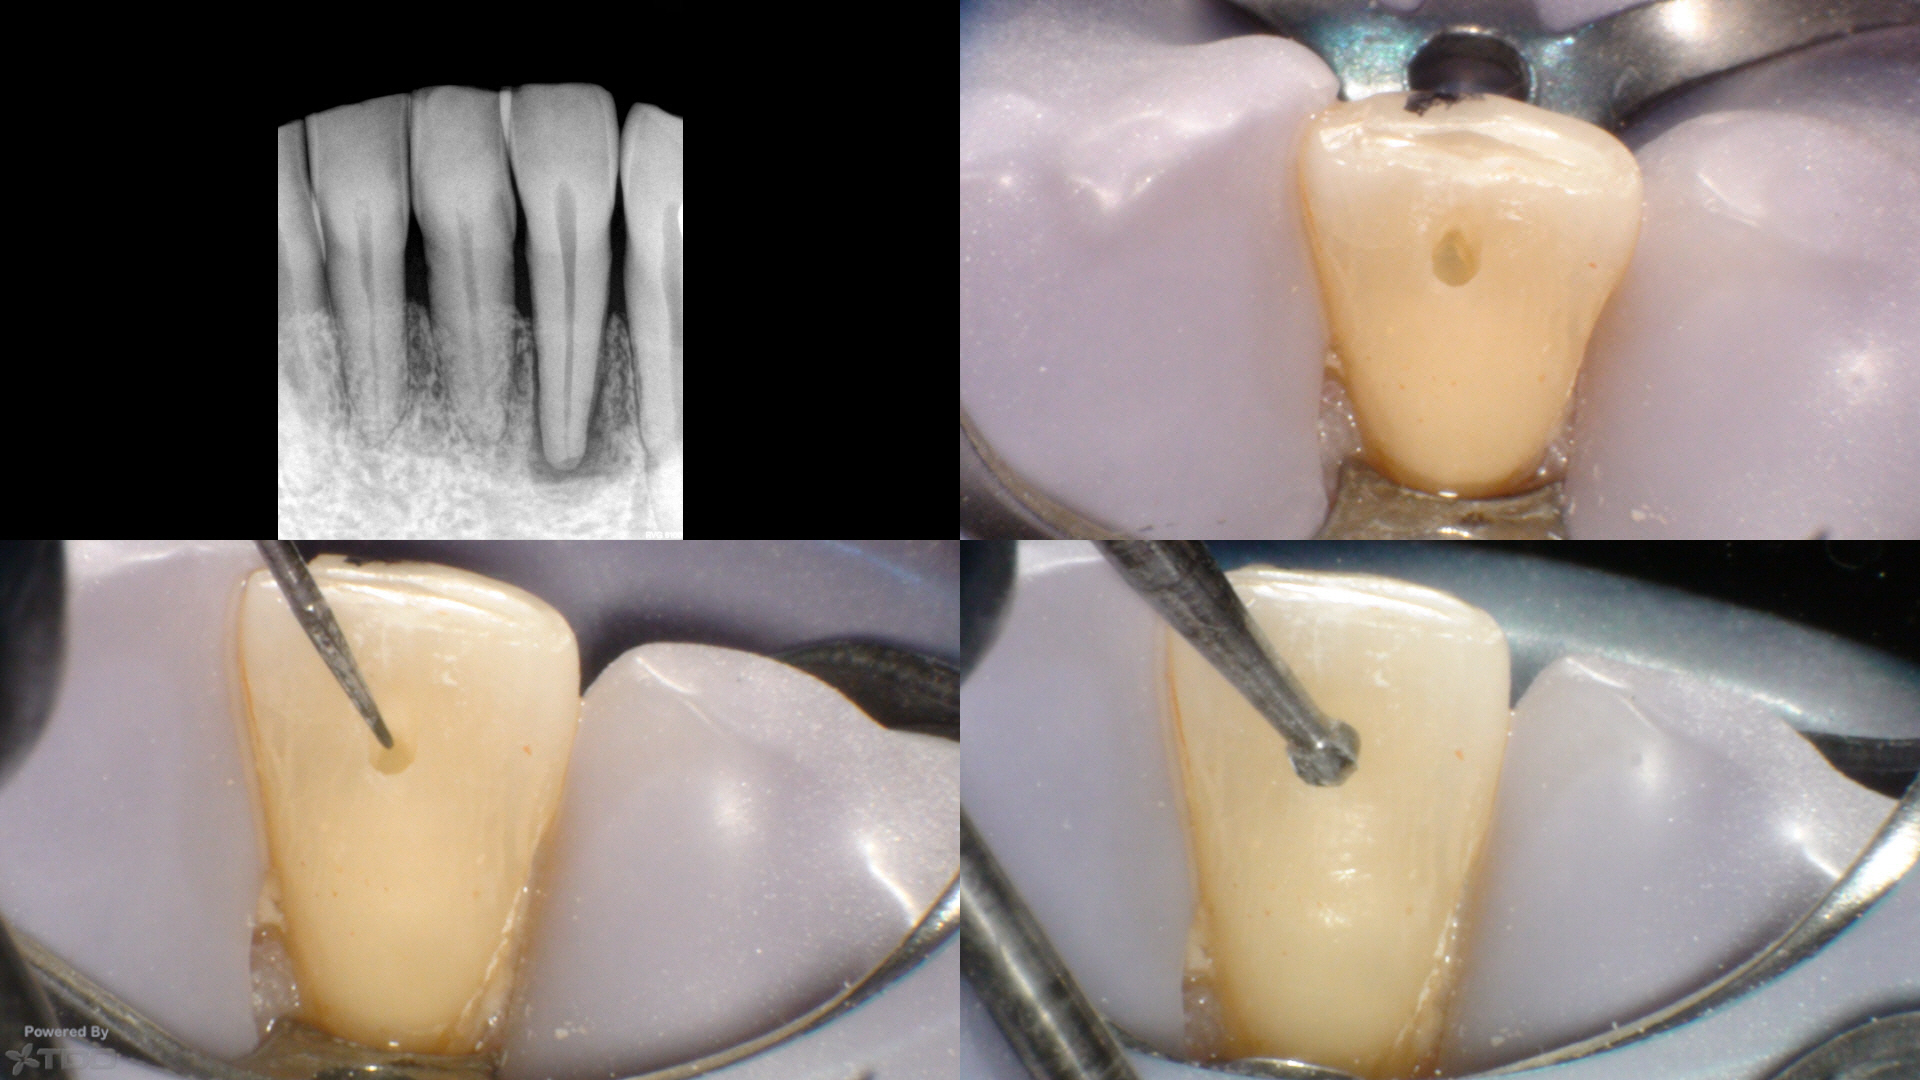

Clinicals show the access with an SS White EG-4 and a round bur which completely covers the access. File clinicials show a SSW 17/V.04 (white band) at length (20mm), am SSW 30/V.06 (blue band) (final shape) and a ProTaper (R) F1 (yellow band) that doesn't even fit in the completed access/shape.